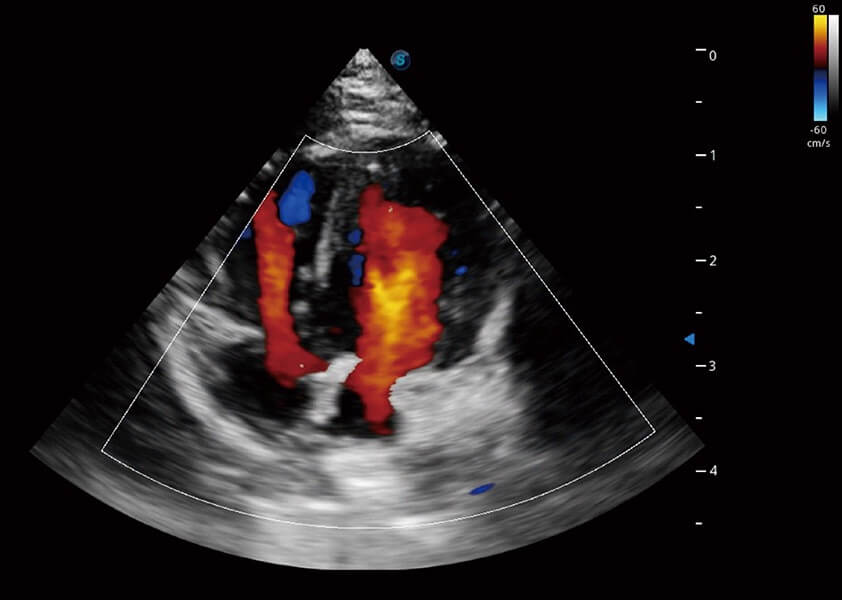

ProPet 60 作为一款高端台式动物超声设备,为动物医生的日常诊断提供了一系列贴合动物临床需求、解决临床实际问题的高级成像功能。凭借全系列高清探头,满足医生对腹部、心脏、生殖、浅表、肌骨等成像的所有需求,切实帮助您提升检查效率,提高诊断信心。